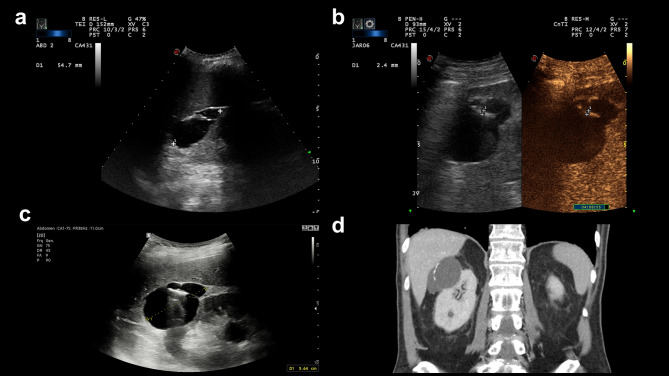

Background: Contrast-enhanced ultrasound (CEUS) is increasingly used in the characterization of cystic renal lesions. Bosniak IIF lesions warrant follow-up, and their reported progression rate remains variable.

Methods: In this single-center retrospective study we assessed renal CEUS exams (SonoVue®) with a diagnosis of Bosniak IIF lesion, conducted between 2015 and 2020. 56 patients (59 lesions) met inclusion criteria. Patient demographics, lesion morphology, follow-up adherence, and outcomes were evaluated.

Results: Significant (p = 0.037) positive correlation was found between patient age and lesion size. 33.9% of patients were immediately lost to follow-up, and they tended to be younger, albeit not significantly (p = 0.09). Recommendation for follow-up imaging was indicated in 66.1% of the initial radiological reports. Follow-up adherence was not significantly lower for lesions with absent recommendation (55% vs. 70.27%, p = 0.26). Fewer (52%) female vs. male (74.19%) patients had a follow-up recommendation (p = 0.1, not significant). 10.8% of the followed lesions demonstrated progression within 5 years. Lesion reevaluation according to the 2020 European Federation of Societies for Ultrasound in Medicine and Biology (EFSUMB) criteria resulted in 77.36% agreement with 22.2% of lesions being downgraded, and a single lesion being upgraded (p = 0.0015, significant).

Conclusions: Follow-up adherence of Bosniak IIF cystic renal lesions was found to be suboptimal, with potential gender disparities. Standardization of follow-up recommendation in the report is an unmet need. Progression rate remains low, but is expected to change with the adoption of novel CEUS-specific criteria. The EFSUMB criteria in particular can improve selection of truly indeterminate lesions.